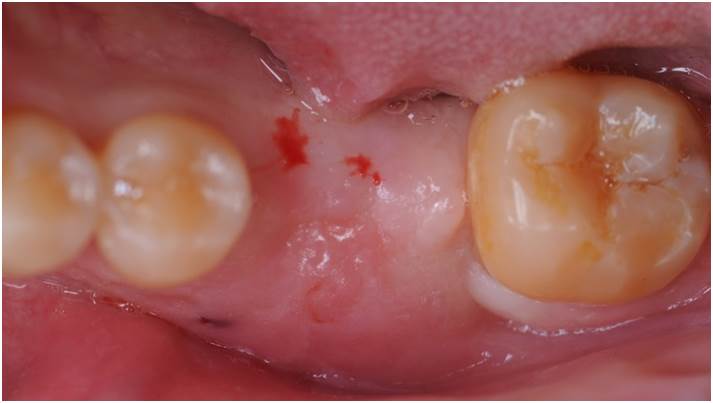

Clinical case: Bone filling into the bottom of deepest thread at 8.0mm AnyRidge fixture

- Courtesy of Dr. Kwang Bum Park -

Keywords

AnyRidge, Knifethread ,extraction socket, ,initial stability ,Allograft, ,osseointegratio ,Dr. Kwang Bum Park, , Mandibular, Single replacement, AnyRidge, Mega-oss,

Products used

Implant system-AnyRidge, Regeneration-Mega-Oss